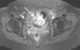

Metastasis from leiomyosarcoma

Leiomyosarcoma, is a malignant (cancerous) smooth muscle tumor. A benign tumor originating from the same tissue is termed leiomyoma. [Source: Wikipedia ]